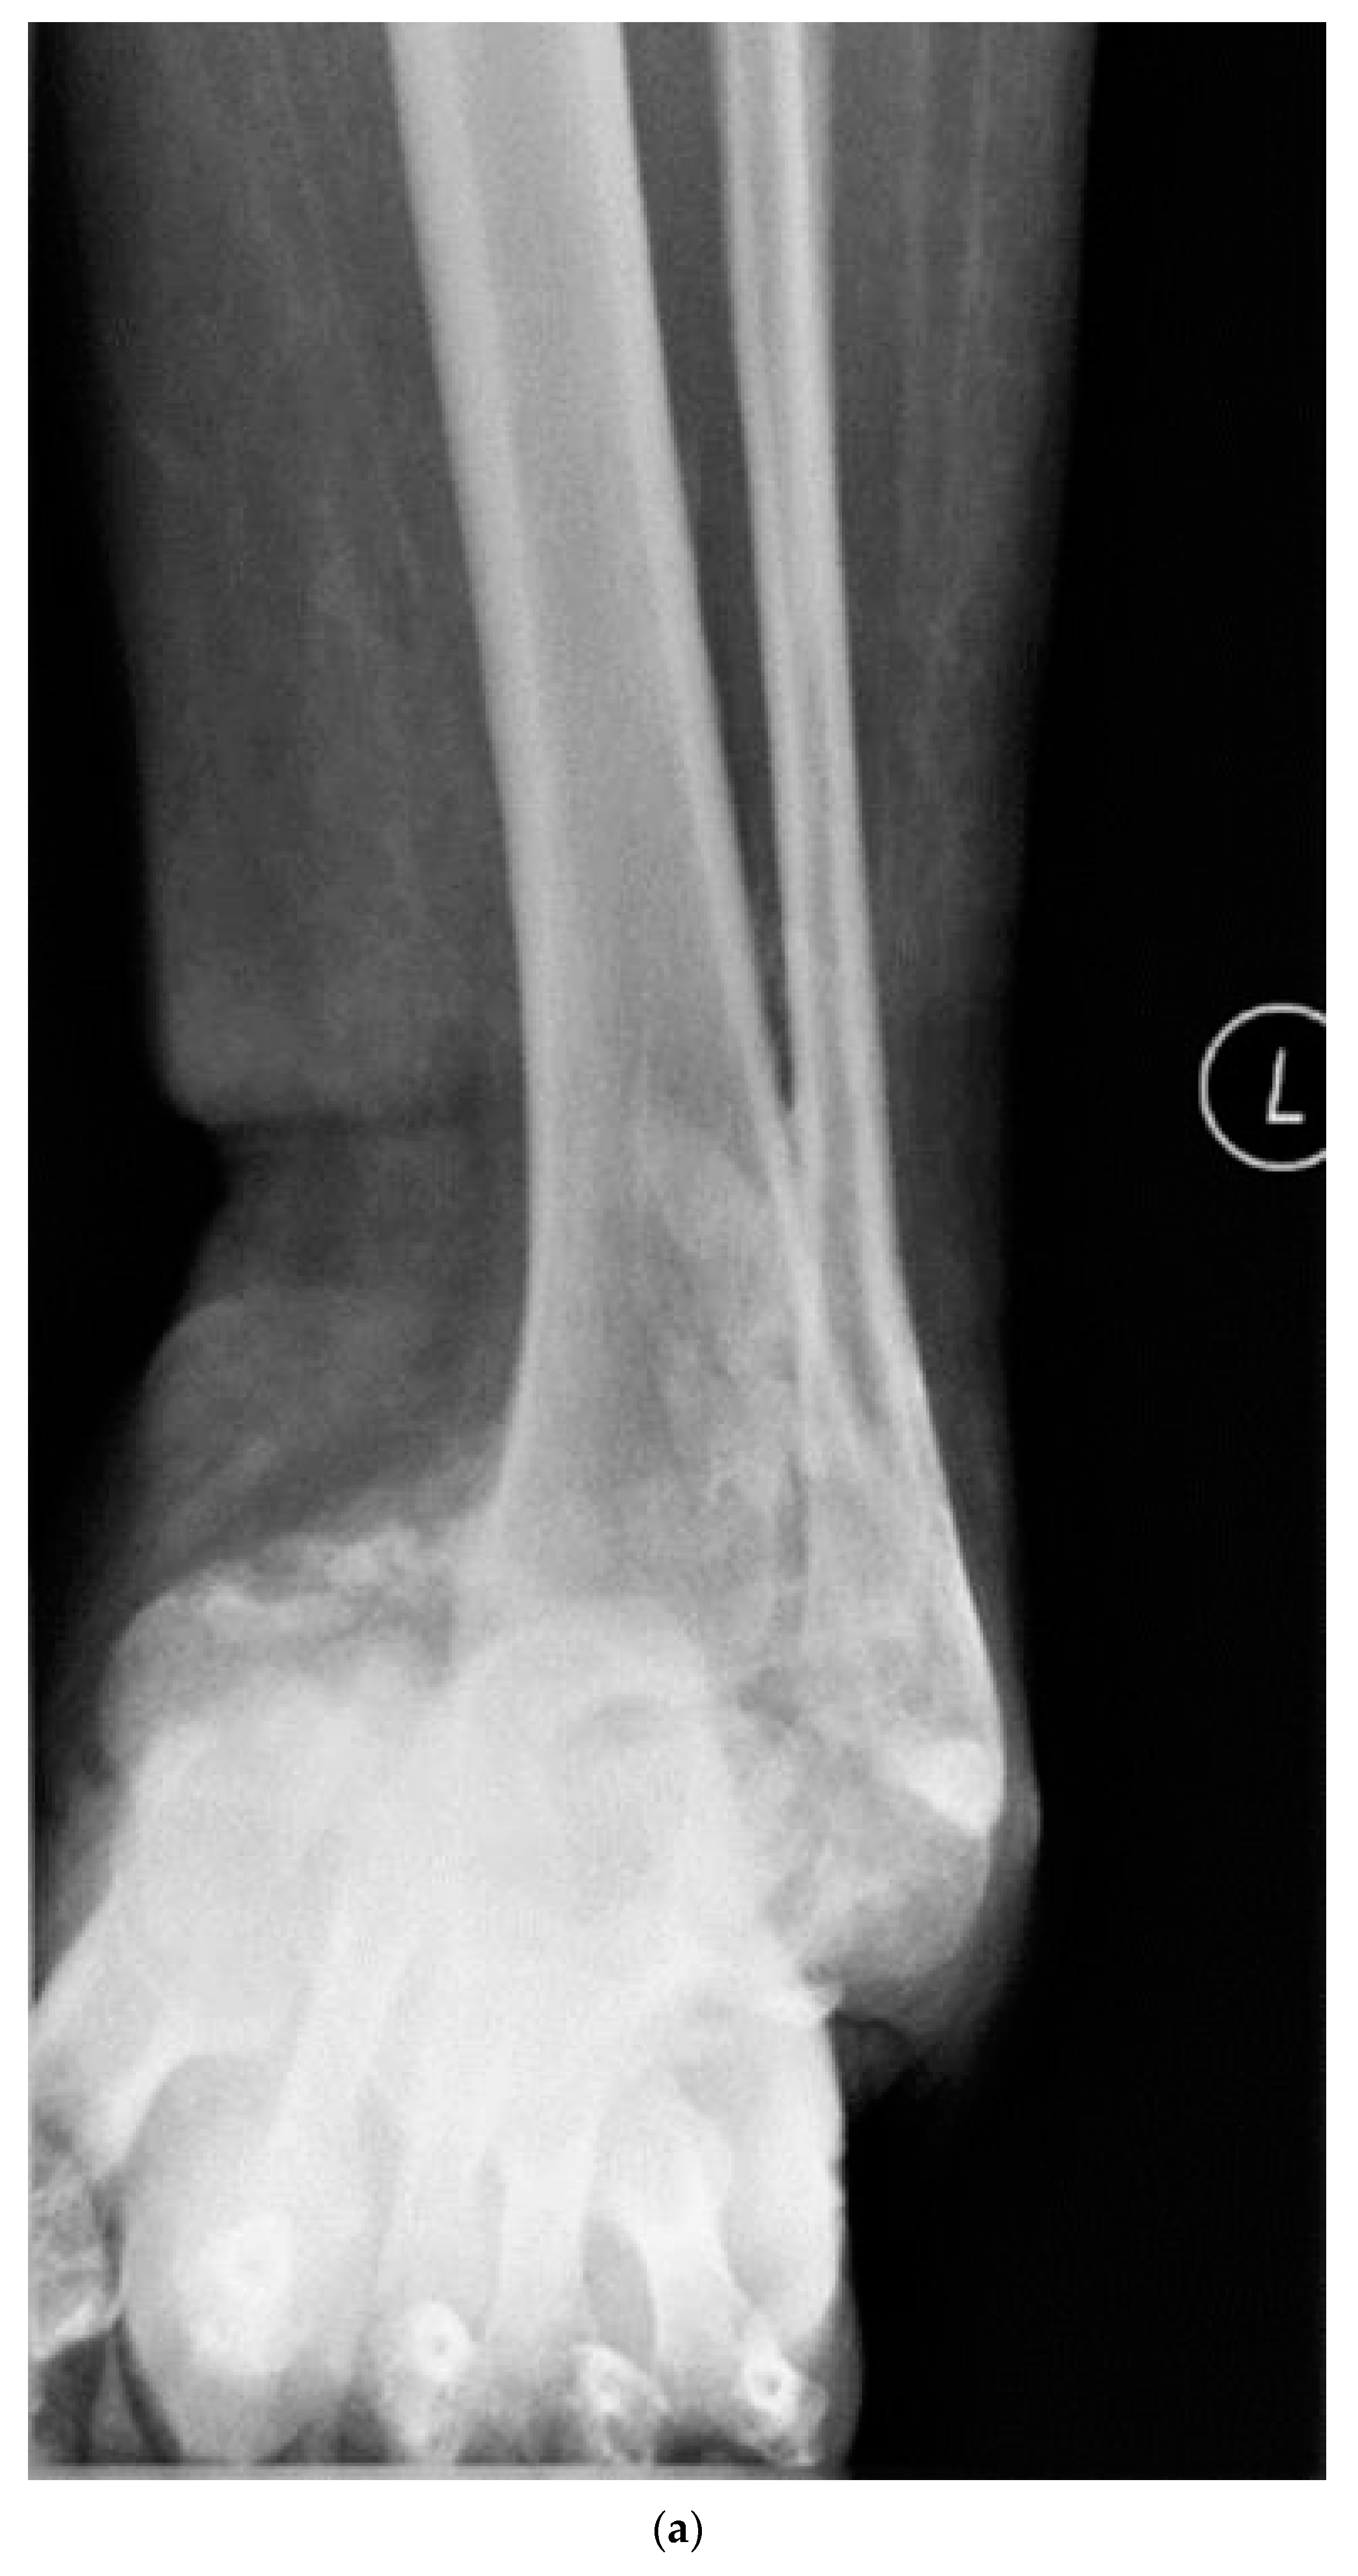

2.4. Surgical Management

- Siebachmeyer, M.; Boddu, K.; Bilal, A.; Hester, T.W.; Hardwick, T.; Fox, T.P.; Edmonds, M.; Kavarthapu, V. Outcome of one-stage correction of deformities of the ankle and hindfoot and fusion in Charcot neuroarthropathy using a retrograde intramedullary hindfoot arthrodesis nail. Bone Jt. J. 2015, 97, 76–82. [Google Scholar] [CrossRef] [PubMed]

- Vasukutty, N.; Jawalkar, H.; Anugraha, A.; Chekuri, R.; Ahluwalia, R.; Kavarthapu, V. Correction of ankle and hind foot deformity in Charcot neuroarthropathy using a retrograde hind foot nail-The Kings’ Experience. Foot Ankle Surg. 2018, 24, 406–410. [Google Scholar] [CrossRef]

- Kavarthapu, V.; Hester, T. Charcot hindfoot deformity reconstruction using a hindfoot nail—Surgical technique. J. Clin. Orthop. Trauma 2021, 16, 277–284. [Google Scholar] [CrossRef] [PubMed]